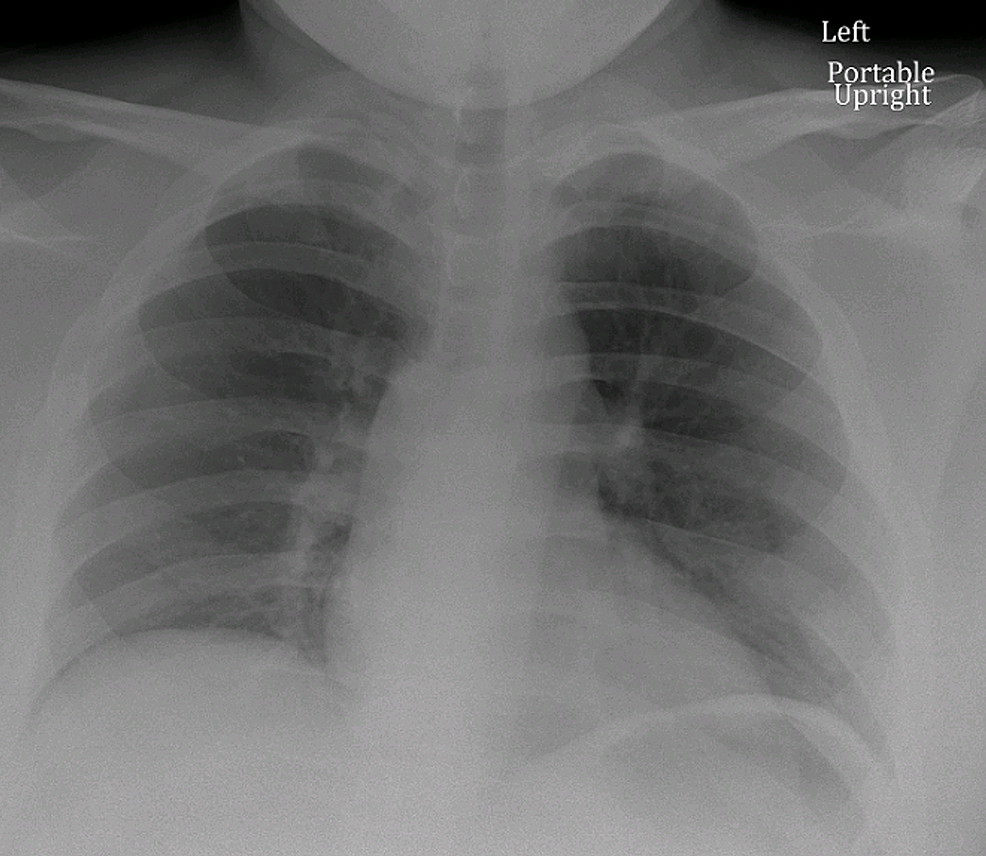

A 19-year-old African-American male with a history of anxiety, prior influenza-associated rhabdomyolysis presented to the ED with a three-day history of worsening bilateral lower extremity myalgias, associated with red-colored urine and a mild dry cough. The remaining review of systems was negative. He denied exercise intolerance and family history was unremarkable for myopathies or neuromuscular disorders. Social history was negative for alcohol, smoking or illicit drug use. He endorsed working in an extended care facility with COVID-19 patients. Believing he may have COVID-19, he presented to the ED. Vitals were normal and the physical exam was remarkable only for bilateral lower extremity tenderness. Complete blood count (CBC) showed leukopenia of 2.4 x 109/L (Range: 4.5-11 x 109/L) with lymphocytopenia of 0.9 x 109/L (range: 1-4 x 109/L). Basic metabolic panel (BMP), renal function, procalcitonin, d-dimer and ferritin were normal. Serum creatine kinase (CK) and lactate dehydrogenase (LDH) were elevated at 284,240 U/L (range: 39-308 U/L) and 2517 U/L (Range: 87-241 U/L), respectively. C-reactive protein (CRP) was elevated at 0.57 mg/dL (range: 0-0.32 mg/dL). The liver panel showed aspartate aminotransferase (AST) and alanine aminotransferase (ALT) were elevated at 1014 U/L (range: 8-34 U/L) and 132 U/L (range: 13-61 U/L), respectively. Urine dipstick was positive for blood but negative for red blood cells (RBCs). Chest x-ray, respiratory viral panel, urine and serum toxicology screen were unremarkable (Figure 1). He was admitted for severe rhabdomyolysis and started on intravenous fluids. He tested positive for COVID-19 and we continued conservative management without antibiotics or hydroxychloroquine. Serum and urine myoglobin were elevated at 23,508 ng/ml (range: 28-72 ng/ml) and 173 ng/ml (range: 0-13 ng/ml), respectively. Viral hepatitis panel, aldolase, thyroid-stimulating hormone (TSH), erythrocyte sedimentation rate (ESR), anti-nuclear antibody (ANA), anti-Jo-1, anti-SSA/SSB, anti-RNP, anti-dsDNA and anti-Smith antibodies were unremarkable. His myalgias continued to worsen, now involving his upper extremities. Serum CK, LDH and AST levels continuously rose, peaking at 694,200 U/L, 13,950 U/L and 2715 U/L, respectively. His renal function and urine output, however, were within normal limits. His symptoms and levels started improving by day 5 with supportive care (Figure 2). Given his history and positive COVID-19 test, it supported COVID-19 presenting as rhabdomyolysis. His renal function, urine output and respiratory function, interestingly, did not deteriorate throughout his eight-day hospital course. During one of his prior hospitalizations for influenza-associated rhabdomyolysis, he underwent an evaluation for metabolic myopathy, which was unremarkable.